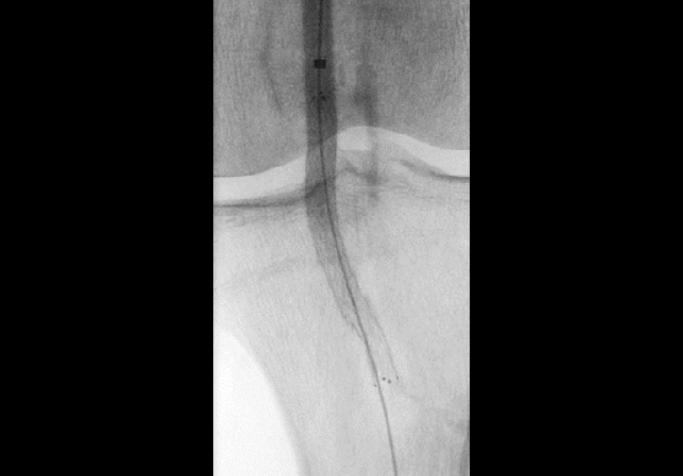

Em procedimentos minimamente invasivos, onde a anatomia pode mudar a cada movimento e as decisões precisam ser tomadas instantaneamente, a capacidade de trabalhar com segurança, rapidez e confiança faz a diferença entre um procedimento eficiente e um repleto de imprevistos.